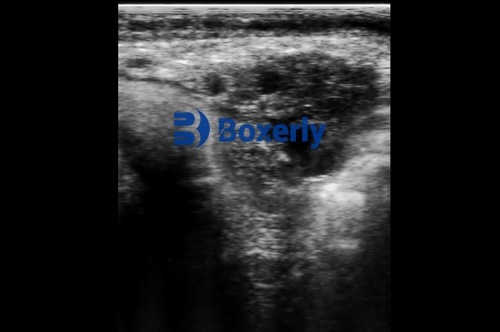

Portable ultrasound gives real-time images of the uterus and ovaries. This is vital for diagnosing uterine infections, monitoring ovarian follicles, or identifying abnormal conditions such as cysts or fluid accumulation.